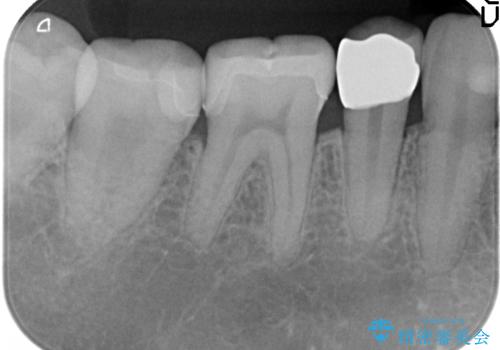

- 右下の奥歯がしみるので診て欲しいといらっしゃった方の症例です。

右下5は虫歯が大きかったため、虫歯を除去後、オールセラミッククラウンによる補綴を行いました。

右下6、7は虫歯を除去後、セラミックインレーによる修復を行いました。

今回用いたオールセラミッククラウンはジルコニアフレームという白い素材の上にセラミックを盛っているため、審美性が非常に高いのが特徴です。

また、ジルコニアは人工ダイヤモンドの材料にも使われているほど高い強度を持っており、そのためオールセラミッククラウンは審美性だけでなく、奥歯やブリッジの補綴も可能とするクラウンです